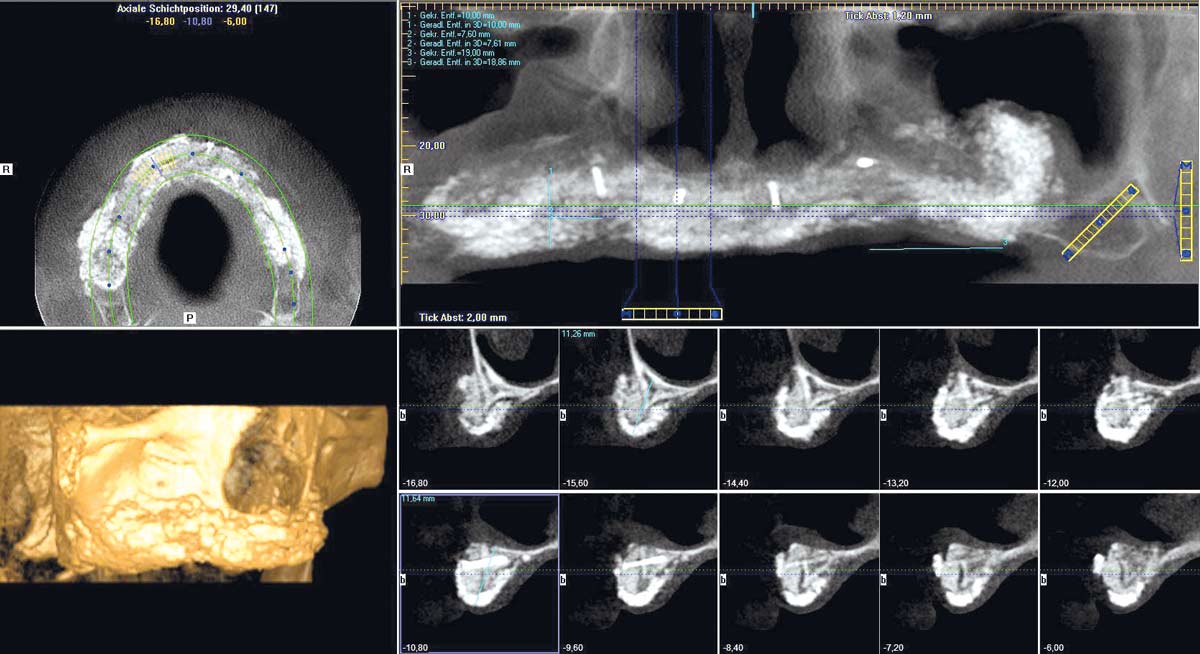

1/23 - Treatment overview – implant planning

Full arch reconstruction of the maxilla with maxgraft® bonebuilder - Dr. M. Erbshäuser

2/23 - Preoperative radiological situation – severely atrophic maxilla